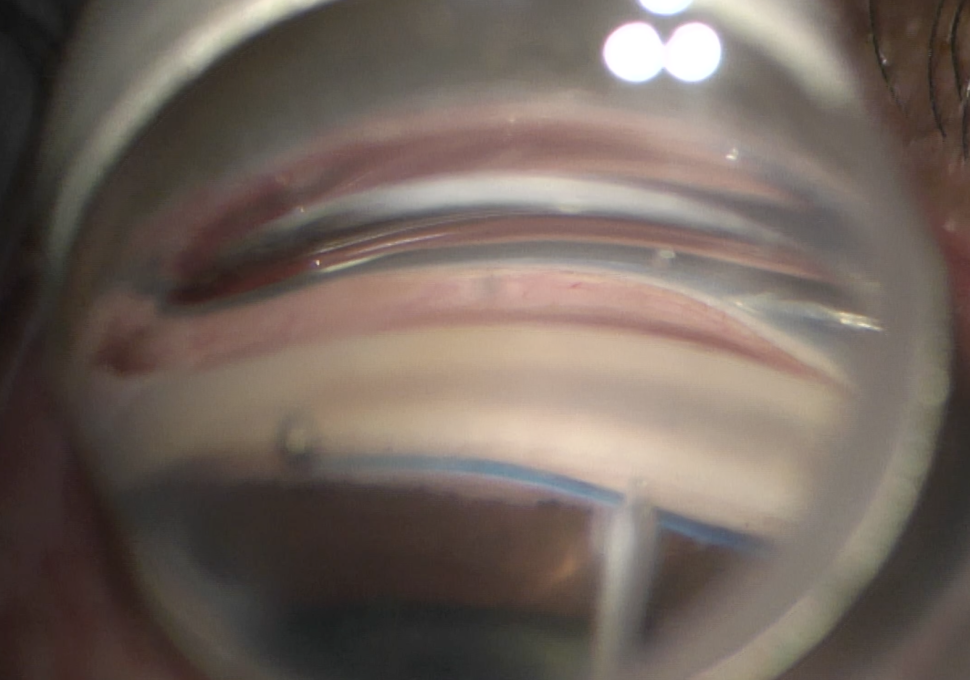

Η εμφύτευσή τους γίνεται με τη χρήση ενός ειδικού φακού (γωνιοπρίσματος) μέσω του οποίου ο/η χειρουργός αποκτούν οπτική πρόσβαση στη γωνία αποχέτευσης του υδατοειδούς και τοποθετούν 2 ή 3 iStents στο γωνιακό δικτυωτό. Η επέμβαση γίνεται σε μονάδα ημερήσιας νοσηλείας με τον ασθενή να γυρίζει σπίτι του την ίδια ημέρα. Πραγματοποιείται συνήθως με τοπική αναισθησία.

Με τη χρήση ενός ειδικού γωνιοφακού, ο/η χειρουργός αποκτούν οπτική πρόσβαση στη γωνία παροχέτευσης του ματιού, δημιουργούν μία μικρή τομή 1-2 χιλιοστών στο γωνιακό δικτυωτό και εισάγουν με μικροχειρουργικά εργαλεία είτε ένα χειρουργικό ράμμα τύπου Prolene ή ένα μικροκαθετήρα με οπτικές ίνες (τύπου iTrack™) στο κανάλι του Schlemm. Όταν ο καθετήρας/ράμμα έχει προωθηθεί 180 με 360 μοίρες μέσα στο κανάλι του Schlemm, με έναν ειδικό χειρισμό αφαιρείται το ράμμα ή ο μικροκαθετήρας και δημιουργείται μια τομή 180 ή 360 μοιρών στο γωνιακό δικτυωτό (Trabecular Meshwork) που παρακάμπτει τα σημεία αντίστασης και παρέχει άμεση πρόσβαση στο υδατοειδές να αποχετευθεί μέσω των αθροιστικών σωληναριών. Η επέμβαση γίνεται σε μονάδα ημερήσιας νοσηλείας με τον ασθενή να γυρίζει σπίτι του την ίδια ημέρα. Πραγματοποιείται συνήθως με τοπική αναισθησία και μέθη υπό την επίβλεψη αναισθησιολόγου.